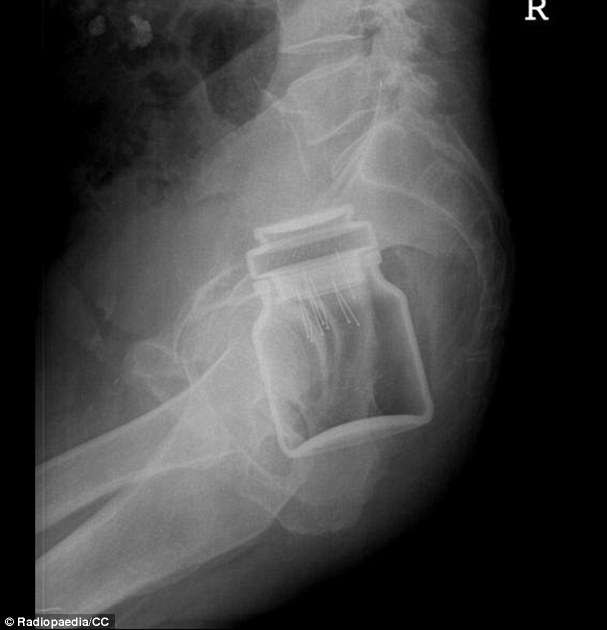

▼美國消費者產品安全委員會(CPSC)發布了2018年急診室就診的數據檔案,發現急診室的醫生不斷的從人類的直腸、下體、喉嚨、耳朵甚至鼻孔取出各種各樣的物品,這些物品的種類包羅萬有,許多甚至會令人感到不可思議!就好像這個案例中,患者直腸中竟然有個咖啡罐!